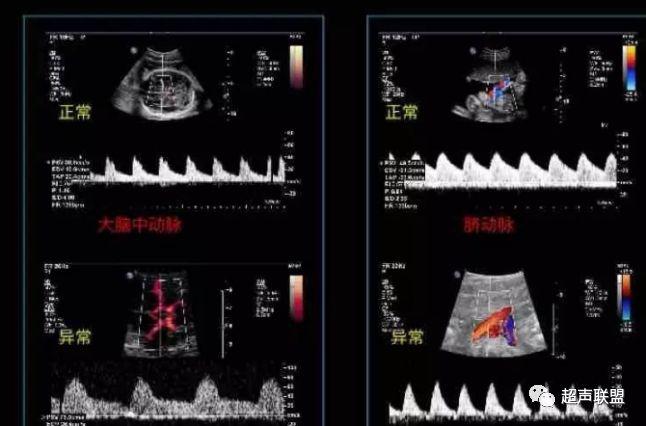

图3 正常大脑中动脉血流频谱

图4 大脑中动脉血流阻力减低

2 胎儿大脑中动脉测定

缺氧早期大脑血液供应增加,颅内血管扩张,阻力降低,舒张末期血流速度增加,PI、RI值下降,说明缺氧早期的血流再分配。当大脑中动脉RI、PI值明显下降,而脐动脉和腹主动脉的PI值升高,大脑中动脉PI值与脐动脉PI值的比值低于2个标准差时,提示严重缺氧的存在。

1、比值标准:大脑中动脉阻力降低,妊娠期,大脑中动脉RI <脐动脉RI;

4、当大脑中动脉RI及PI值明显下降,而脐动脉及腹主动脉的PI值之间升高,大脑中动脉PI值与脐动脉PI值低于两个标准差时,提示为胎儿严重缺氧;

2、大脑中动脉血流阻力降低;